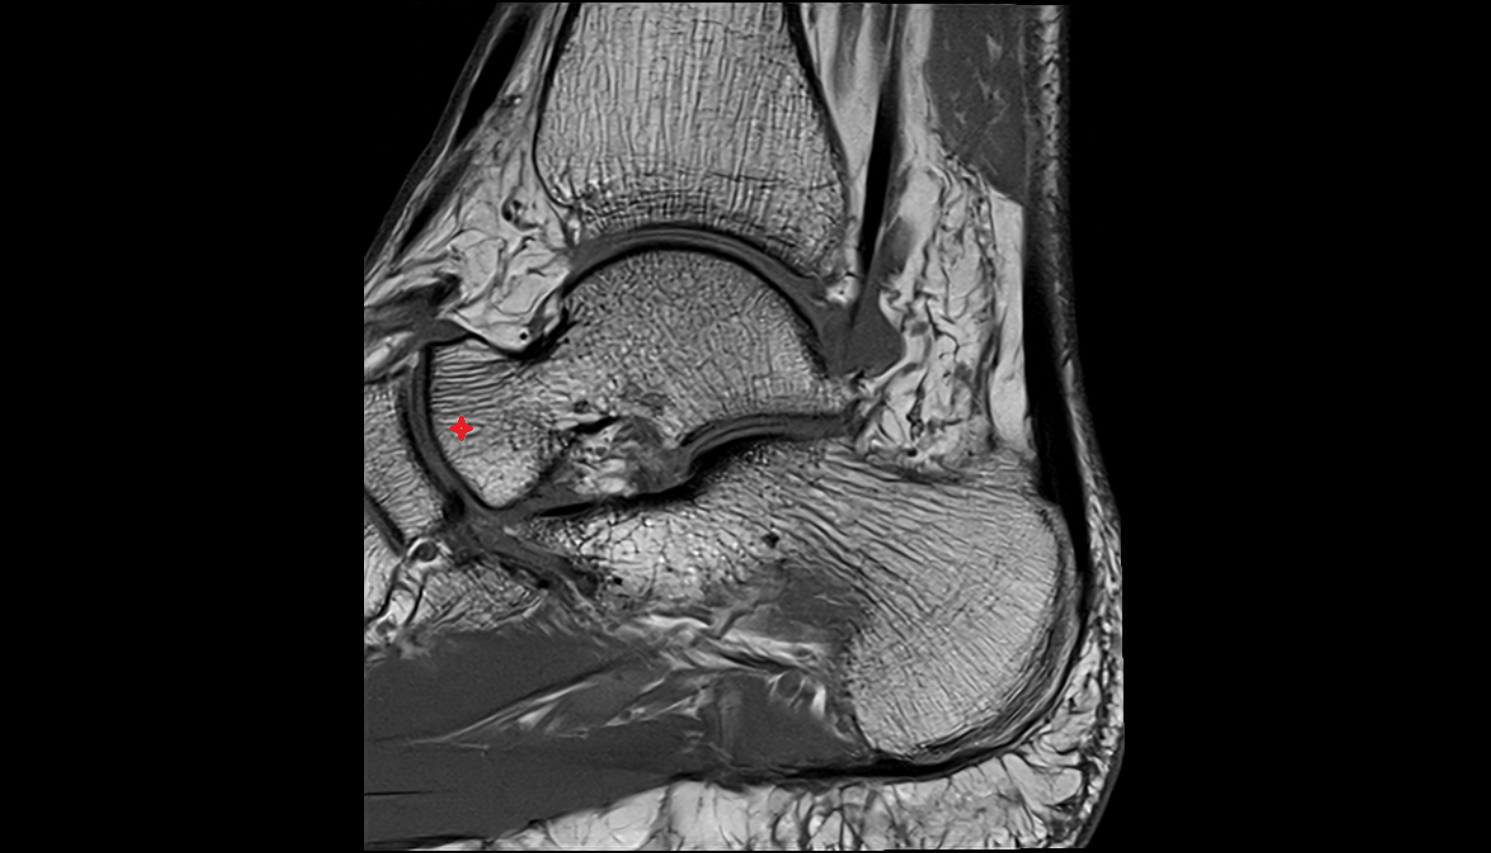

- Talus

- Head of talus

- Body of talus

- Neck of talus

- Calcaneus

- Ankle joint

- Talocalcaneal joint

- Achilles tendon